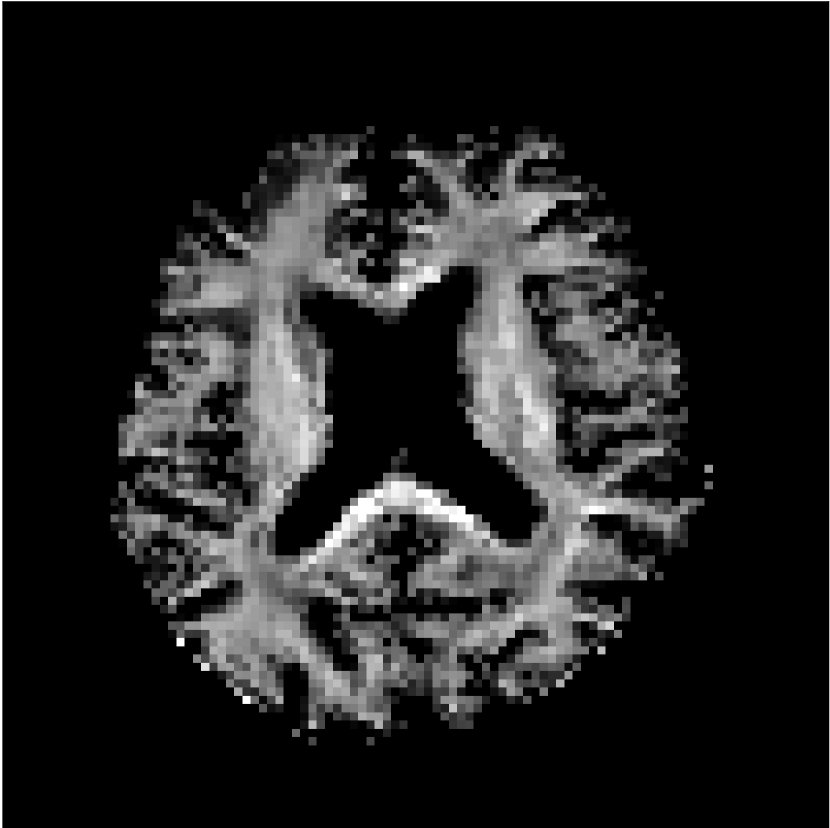

Figure 8 shows examples of non-diffusion-weighted images before and after processing. The raw images (Raw) served as the input for the magnitude deep learning (MCNN) and complex deep learning (CCNN) methods.

Raw

MCNN,

MCNN Resid.,

CCNN,

CCNN Resid.,

No PF

5/8 PF

Both methods remove artifacts, but the MCNN method allows residual rippling artifacts to pass through in the presence of partial Fourier. These rippling artifacts are not present in the CCNN method.